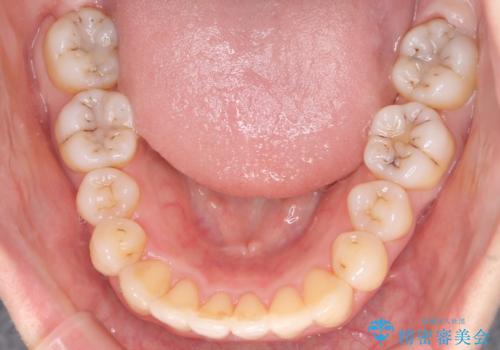

前歯が前後反対にかんでいる インビザラインによる目立たない矯正

歯と歯の間をわずかに削り、ガタガタを改善しました。

目立たずに矯正を終えることができて、喜んでいただけました。